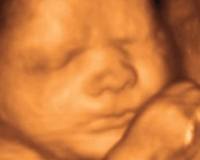

Les échographies 3D pourraient être dangereuses

Le Collège national des gynécologues et obstétriciens français tire la sonnette d'alarme. De nombreux futurs parents font en effet appel à l'échographie 3D pour découvrir le visage de leur bébé, pour une centaine d'euros.

Cette pratique qui n'a pas de finalité médicale pourrait être dangereuse pour les foetus par l'exposition prolongée aux ultra-sons qu'elle induit.

Là où une échographie normale dure peu de temps et ne soumet aucune partie du corps du bébé à une exposition constante et prolongée, la 3D menace les organes les plus fragiles : les yeux et le cerveau. D'autant que la plupart du temps, ces examens ne sont pas pratiqués par des personnels formés.